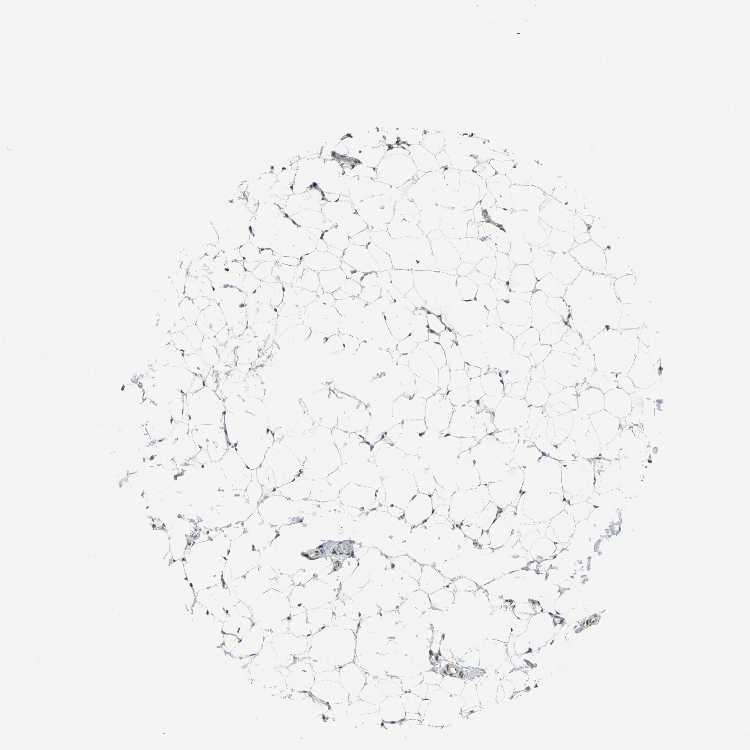

SOFT TISSUE 1 - Antibody stainingi

Antibody staining in the annotated cell types in the current human tissue is reported as not detected, low, medium, or high, based on conventional immunohistochemistry profiling in selected tissues. This score is based on the combination of the staining intensity and fraction of stained cells.

Each image is clickable and will lead to virtual microscopy that enables deeper exploration of all samples and also displays staining intensity scores, fraction scores and subcellular localization as well as patient and tissue information for each sample.

Antibody HPA006628

Fibroblasts Medium

Peripheral nerve Not detected